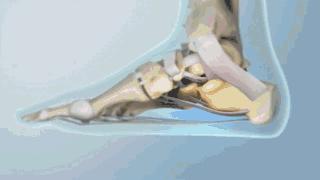

足底筋膜炎又称为“跖筋膜炎”,或俗称“跟痛症”,是指足跟和足底部分纤维组织出现的一种慢性无菌性炎症,是由足跟着地时反复高张力刺激足底筋膜的起点造成轻微的撕裂,引起囊腔状的退行性改变。

而骨刺就如下图中所示,则是这种慢性炎症反复刺激跟骨后产生的反应性增生,从一定程度上反而可以缓解疼痛。